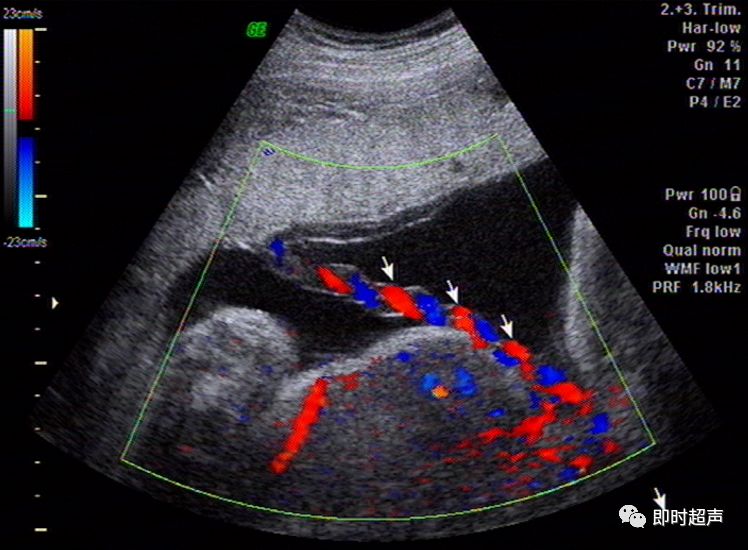

胆囊肿瘤性病变的超声诊断

典型"火海征" - 超声医学讨论版 - 爱爱医医学论坛 - 爱爱医医学网